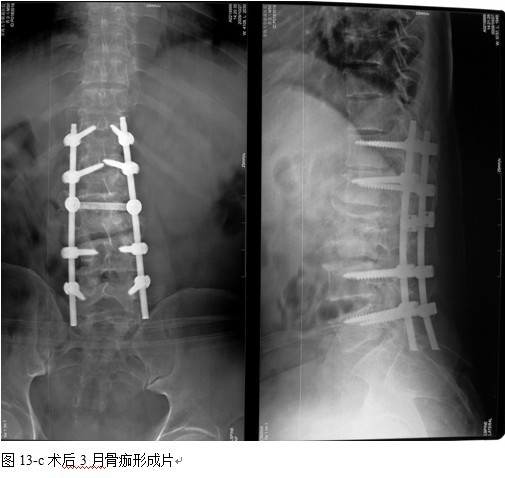

本组手术用时间3~4h , 平均3.5h 。术中出血300~500ml , 平均约350ml 。术后症状完全缓解,无神经功能障碍加重等并发症,1例营养差的老年患者伤口出现窦道,1例因肝功能差,术后未口服抗痨药,伤口出现窦道,经换药后二期愈合,其余病例伤口均一期愈合。马尾神经受损的患者术后基本恢复正常。术后一周后凸角平均 5.4°后凸畸形平均矫正90%以上, 最终后凸角平均8.3°,后凸角度平均丢失4.2°。随访3个月有87%(40/46)有骨痂形成,6个月91.3%(42/46)明显骨性愈合(见图),其余4例9-12个月内愈合,随访时间3-32个月,平均11个月,46例患者中2例在术后2个月和3个月时背部形成脓肿,换药后治愈。2例出院1月后并发结核性脑膜炎,治疗后好转。1例因椎弓根钉偏外,刺激神经根,5个月后从侧方脱出,疼痛加重,因前后路植骨完全愈合,取出后症状完全缓解。

4.1腰椎结核手术治疗中应用内固定的必要性和安全性:为了预防和矫正畸形,稳定脊柱,减少结核的复发率以及提高病变节段的融合率,让患者早期下床功能锻炼, 国内外学者将内固定用于脊柱结核的手术治疗中,取得了令人满意的效果[4、5、6、7、8、9、10]。通过本组病例观察,我们发现内固定的应用有着重要的作用,内固定不但可以预防,矫正后凸侧弯畸形,而且畸形的矫正率明显提高,未见畸形加重和矫正的明显丢失,还能使病变节段在术后即刻获得足够的稳定性, 为脊柱融合和结核病灶的静止提供一个良好的力学环境,促进了植骨融合,未见植骨块的吸收,移位和假关节的形成,术后结合支具治疗,大大缩短术后卧床时间,简化术后护理,利于患者全身情况的改善及后续康复治疗。

中国学者金大地[22]等采用一期前路病灶清除植骨前路钢板固定治疗腰椎结核,平均18°的后凸畸形得以矫正,Mukhtar[23] AM等采用前路病灶清除植骨分期或同期后路固定治疗腰椎结核22例,术后后凸畸形矫正度数平均为27°。从我们的随访结果看,术后后凸畸形平均矫正度数为26.9°,后凸畸形平均矫正90%以上, 6个月-49个月后随访,后凸角度平均丢失4.2°。本术式也适用于结核所引起的弹性差的后凸畸形,对于病灶纤维化或骨化的非弹性后凸畸形,后路固定后,先行前路病灶、纤维化或骨化切除、松解,逐步刮除病灶、逐步撑开,达到畸形矫正和植骨的目的。